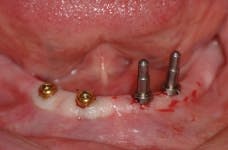

The ScrewIndirect one-piece implant offers a 3.0 mm D implant with adequate strength. All four diameter options (3.0 mm, 3.7 mm, 4.7 mm and 5.7 mm) have the same 5 mm D multi-unit platform. The 3.0 mm D implant allows treatment of narrow ridges and simplifies accurate placement during flapless surgery. Providing teeth in one day to edentulous patients and immediate implant placement following extractions is becoming the treatment of choice. The patient's existing denture is converted to a fixed-detachable prosthesis immediately following implant placement. This is accomplished by attaching titanium sleeves to the implants that project through holes cut in the denture and attached them to the denture with cold-cure acrylic followed by shortening the denture flanges.